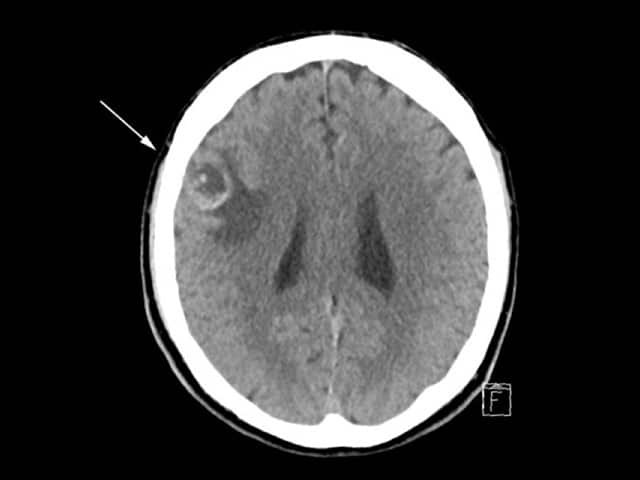

CT scan of brain with melanoma metastasis

Although primary melanoma tumours and local metastases in the lymph nodes or in-transit can often be detected on clinical examination, clinical monitoring for deep lymph nodes and distant viscera is more difficult. Distant visceral metastatic disease is often asymptomatic until advanced, when it may be difficult to remove surgically [1].

Basic radiological investigations such as chest x-ray (CXR) can detect occult metastatic melanoma, but their two-dimensional soft-tissue views are limited [5]. Thus many patients will be referred for CT, positron emission tomography-CT (PET-CT), ultrasound imaging, and MRI scans.

CT and PET-CT scans are commonly used in staging and surveillance of many solid malignancies.